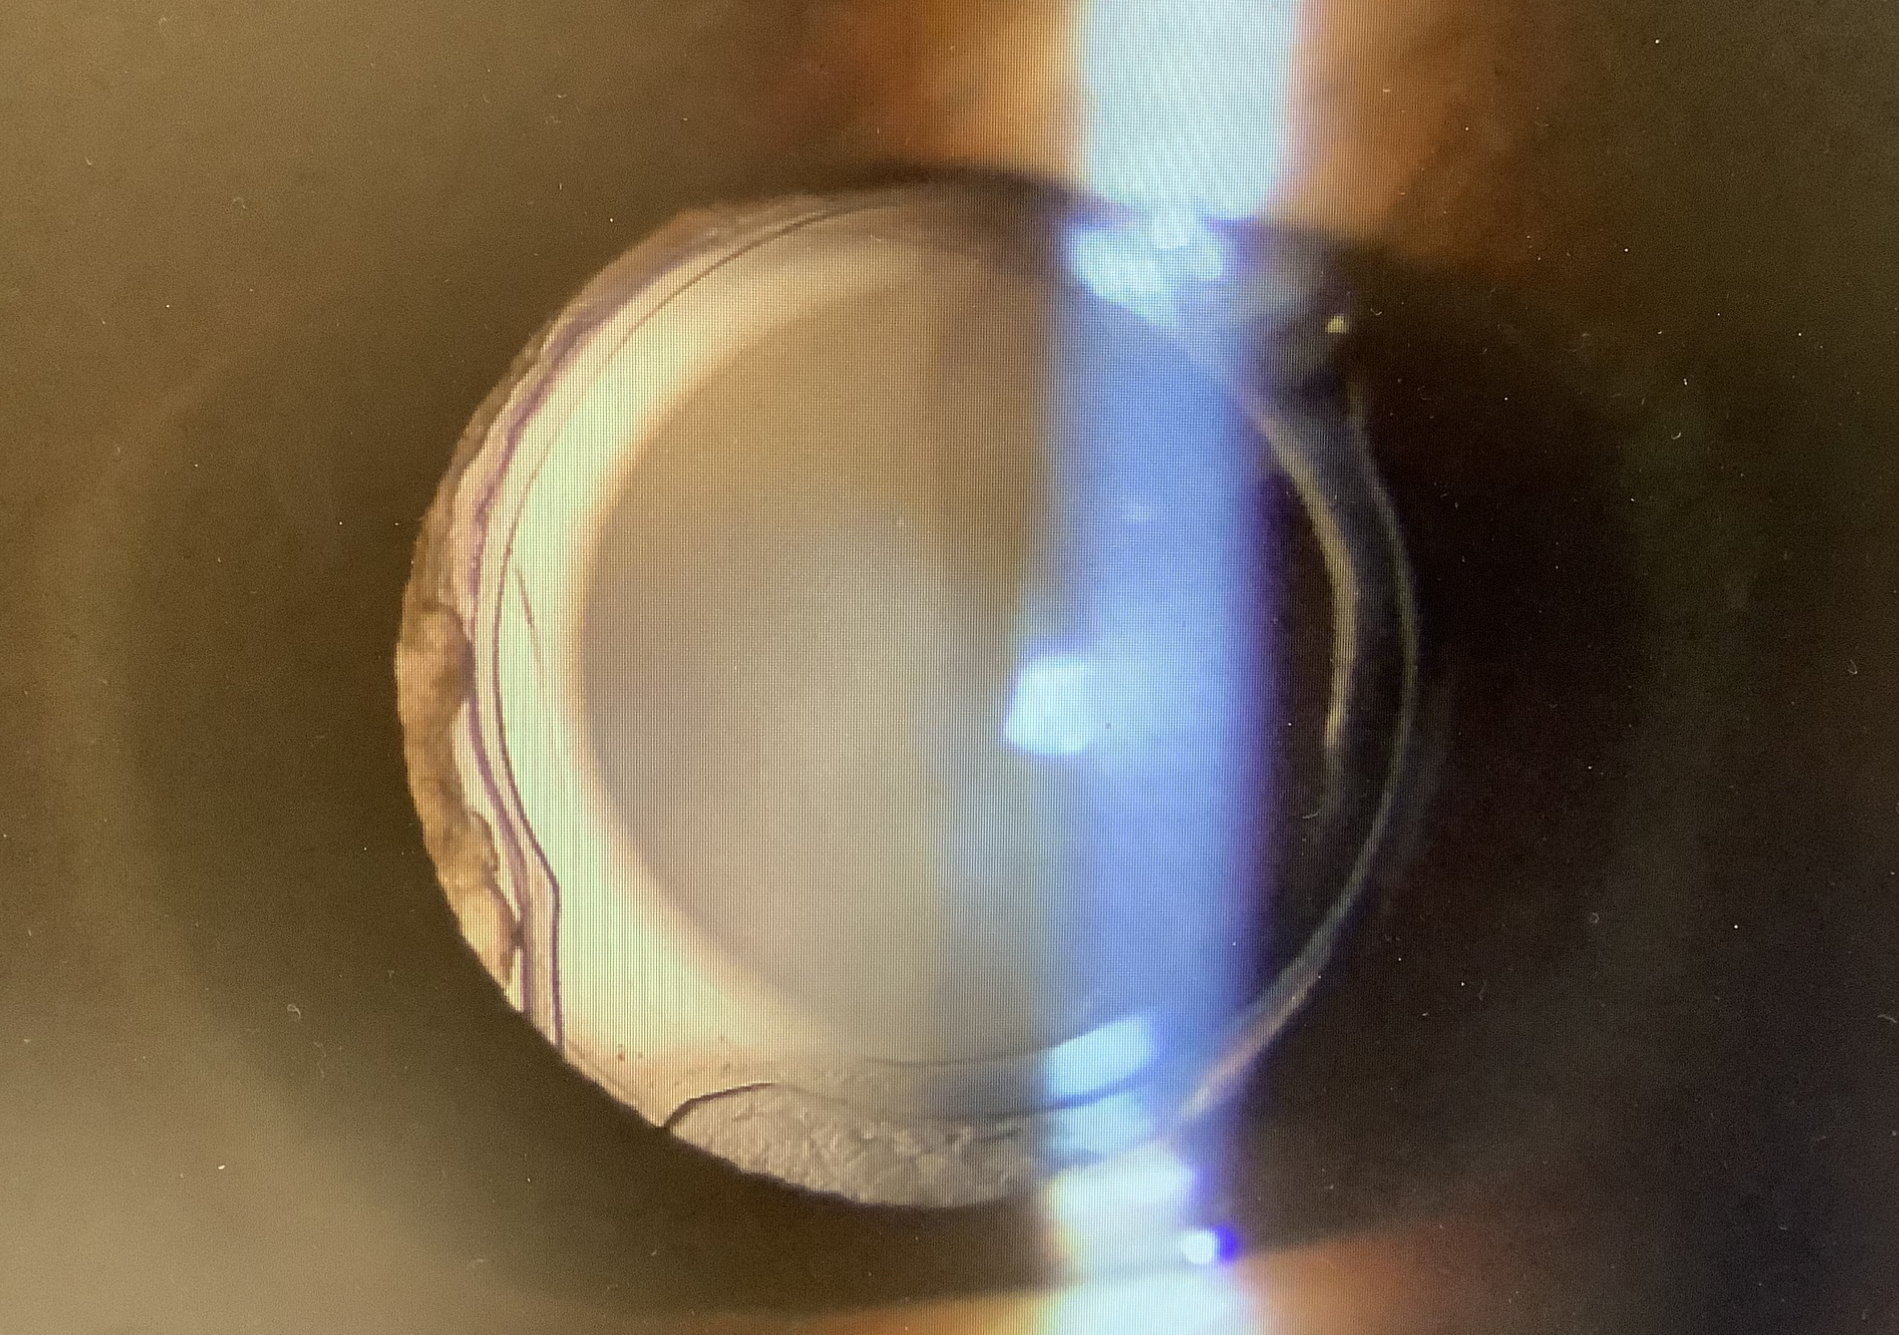

昨日の手術では、50代の女性の眼内レンズの取り出し(レンズ摘出)をさせていただきました。この患者さまは、6年前に他院で右眼の白内障の手術を受け、その後から、頭痛や眩暈などの違和感や不快症状に悩まされるようになり、レンズの摘出を希望されました。円錐角膜があるため、裸眼視力は0.3程度でしたが、レンズ自体はきれいに入っており、診察や検査上は手術や経過に問題ないように思えましたので、レンズを取り出して症状が改善するのかは正直、分かりませんでした。また、手術にはリスクもありますし、かえって見えにくくなってしまう可能性もなくはありませんでしたし、所見上、問題ない眼に対しての治療で保険診療の適応にはならず、手術するとなると自費での対応をせねばならない問題もありました。しかし、それらを考慮しても、なんとしてもレンズを取り出したいとおっしゃってくださり、その真剣で切実なお気持ちがとても伝わってきましたので、この手術を引き受けよう、というか、引き受けなければならないと思い、手術をさせていただきました。

白内障の手術から6年経っていましたが、幸い、レンズの癒着は剥がれ、きれいにレンズを取り出すことができ、術翌日の今日の診察でも眼の状態は非常にきれいで、不思議なことに裸眼視力も0.4と思った以上に見えていて、何より、ご本人の感じ方が、『今までのイヤな見え方、症状がなくなりました』とおっしゃってくださり、本当によかったです。僕が診て問題となる所見がなく、医学的な見地からは根拠が持てなくとも、患者さまが異常と感じることはあり、その感覚を信じて治療すると改善することもあるというよい例だったかもしれません(僕のところへいらっしゃる前にもいくつもの眼科を受診され“問題ない”と診断を受けていたそうです)。この患者さまは遥々、広島から来てくださいましたが、遠くからでも来た甲斐があったと思ってくださったら、よかったと思います。頑張って、手術を受けてくださり、ありがとうございました。